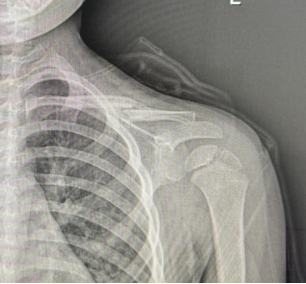

朱某,男,2016-3-15出生,因“跌倒致左肩疼痛伴活动受限2小时”2019年12月12日来我院门诊。检查发现左锁骨区见肿胀、畸形,明显压痛,左肩活动受限。本院X线摄片示:左锁骨骨折,断端明显重叠移位(图1),予以8字绷带外固定制动,定期随访。2020年1月17日复诊述左肩无肿痛,活动基本正常,摄片示:左锁骨骨折,断端对线欠佳,局部明显骨痂形成(图2)。2020年6月8日再次复查摄片示:左锁骨骨折,断端对线可,已骨性愈合(图3)。2023年9月26日再复查摄片示:左锁骨骨折部位已完成塑形,与健侧无明显差异(图4)。

图2 明显见骨痂形成